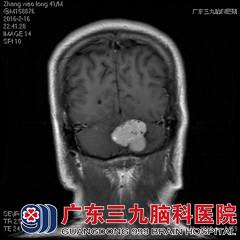

术后张先生恢复良好,术后第3天便可下床行走,且无并发症出现。之后张先生转至肿瘤科进一步接受放疗治疗。

术后复查核磁显示病灶切除